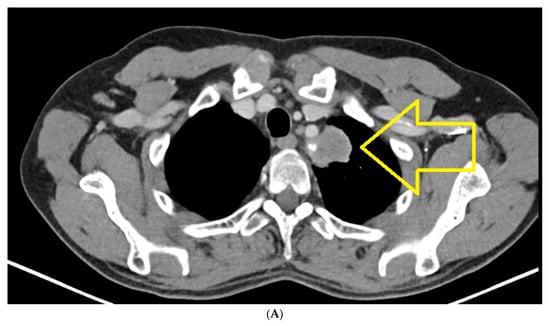

CT of chest, abdomen and pelvis from August 2021 highlights the left upper lobe lung tumor, which was discretely increased in size compared to the previous examination; a right adrenal node also newly appeared was identified (secondary) (Figure 1A,B).

Figure 1.

(A) Chest CT August 2021: left upper lobe lung tumor. (B) CT abdomen August 2021: right adrenal node newly appeared (secondary).